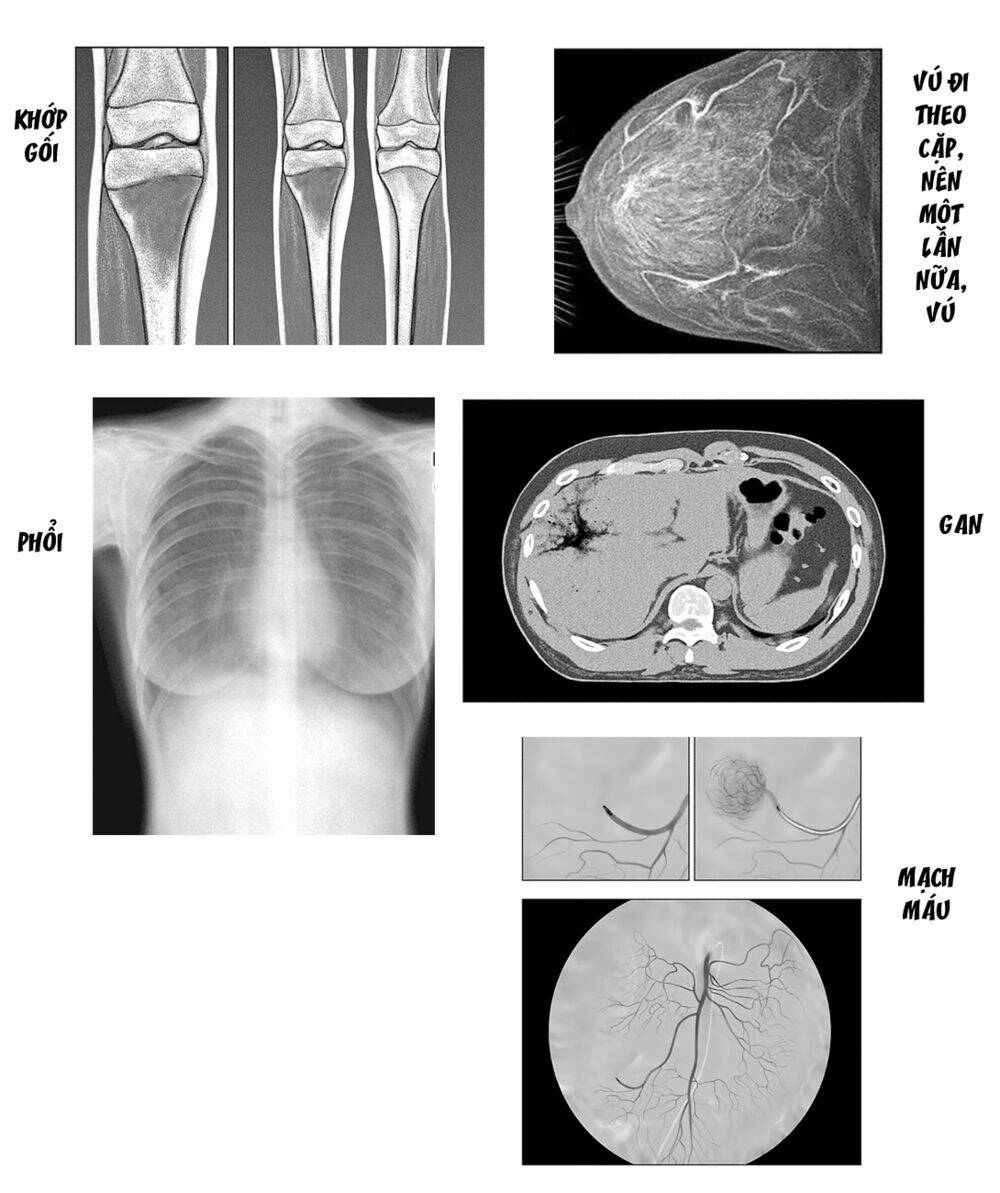

Radiation House

— chap 50